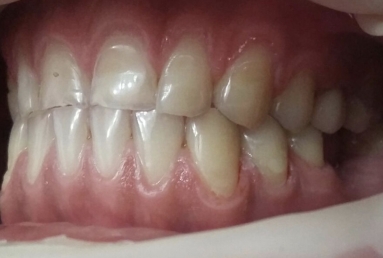

Then fixed orthodontic treatment is set for almost 2 years, so moving the teeth a new more favorable position is obtained to create space for veneers. After wax up a mock up is done for provisional veneers and the new occlusion is tested.

The final porcelain veneers for all frontal maxillary teeth are completed with tooth whitening and changing some composite fillings in lower frontals. On the lower left side a dental implant is inserted, on the upper right side external sinus lift is done. the treatment will be finalised with another upper implant, then two crowns on implants.